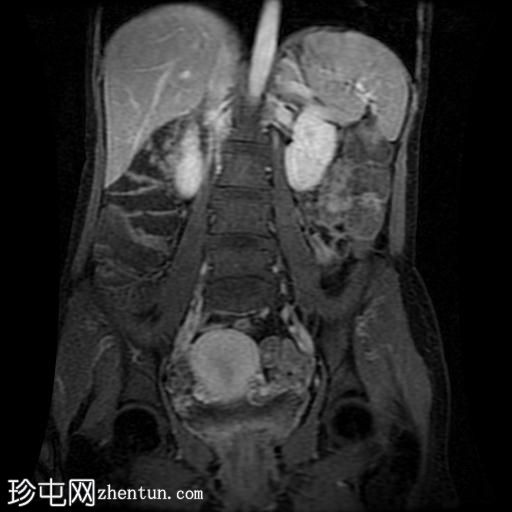

冠状位T2加权像

脂肪抑制

回肠末端及盆腔回肠肠袢可见长段肠壁增厚及强化,肠周血管丰富,呈“梳状征”,并可见明显的纤维脂肪浸润。

未见瘘管、积液、腹水或梗阻。

磁共振肠道造影(MRE)结果支持克罗恩病的诊断,显示远端及末端回肠以活动

性病

变为主,并可见明显的肠周血管。